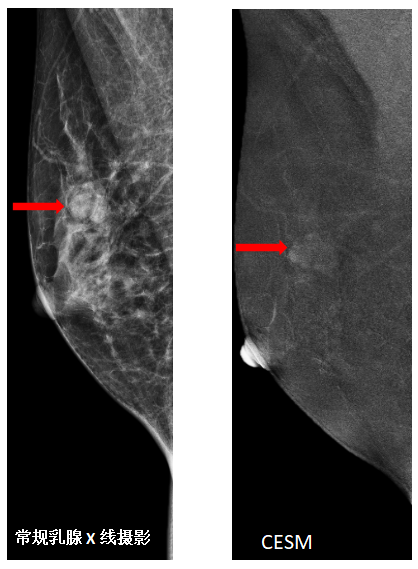

CESM

CESM(Contrast Enhancement Spectral Mammography)对比增强乳腺检查技术。其原理是利用碘造影剂,同时采集低能和高能数据并重建同一位置的两幅图像一套为(似传统MG)低能图像;另一套为能量减影图像:有效消除背景及腺体组织,仅保留碘剂代谢异常的乳腺病变。

CESM的优点是:该技术结合了数字化乳腺摄影与对比剂特性来提高病灶的检出,同时实现对实质肿块及微钙化的显示;对乳腺病变阳性检出率提高20%,临床价值不亚于MR且特异性提高 5%,还可以减少假阳性率和不必要的活检与手术;可显著提高乳腺 X 线摄影的敏感性,特异性,其敏感性与磁共振一致,特异性更好,费用更低。什么情况下做CESM检查:如致密性乳腺;高危患者筛查与临床诊断;明确病灶,判断范围,指导治疗;治疗后评估,判断残留或复发;排除假阳性。